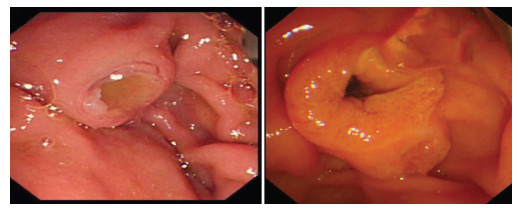

Endoscopic retrograde cholangiopancreatography combined with Spyglass in diagnosis of common bile duct papillary myxoma: A case report

Xuan DING, Linheng WANG, Gui JIANG, Yifei YUN, Xinyu LU, Yupu YAO

2021, 37(12): 2902-2904. DOI: 10.3969/j.issn.1001-5256.2021.12.034

Abstract(1379) HTML (223) PDF (2331KB)(56)

Abstract: